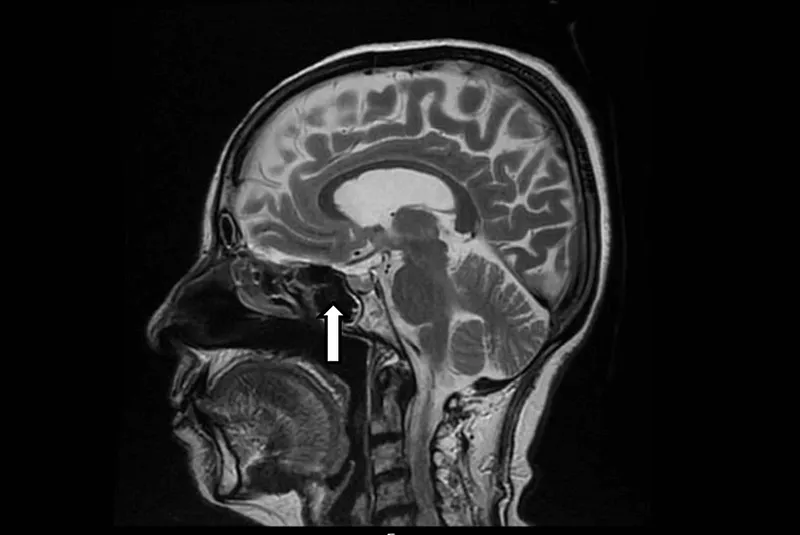

- Location: Sella turcica of sphenoid bone.

- Visual: Bitemporal hemianopia (optic chiasm compression).

⭐ Bitemporal hemianopia is the commonest visual defect from a pituitary mass compressing the optic chiasm.